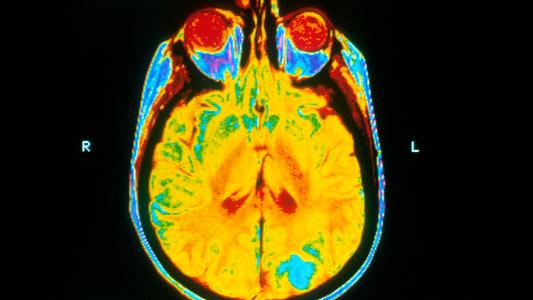

The bacteria itself, Mycobacterium tuberculosis, is weakly gram-positive, rod-shaped, and has numerous tricks that make it hard to fight. This includes a number of genes that help it evade the immune system and protect itself from drugs, along with a waxy coating that’s tough to penetrate. It has ways to distract and dampen the immune system around it.